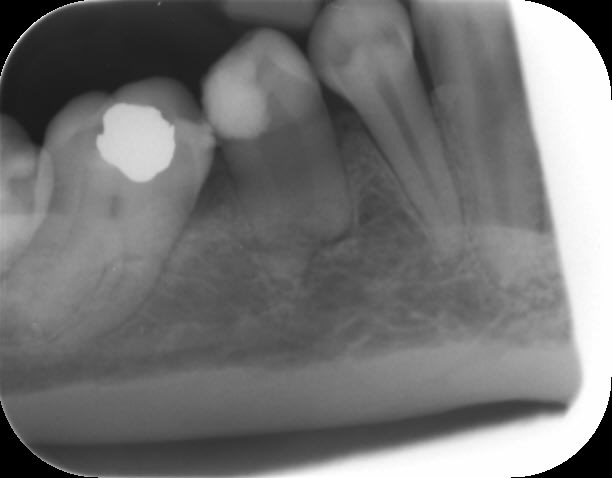

C'est une prémolaire en rotation.

Intéressant de voir ces dents de profil.

Je pense à l'article sur le système Saf dont on parle dans le Dentoscope que vous avez peut-être déjà lu, avec un rappel sur l'anatomie de ces canaux souvent très éloignée de la projection mentale que nous donnent nos radios.

Bon quand j'ai eu la première radio je me suis dit bon sang l'infection a vraiment bien bouffé cette dent à l'apex et elle m'a tout l'air de ressembler à une taurodonte.

La 2è radio m'a dit arrête-toi là !